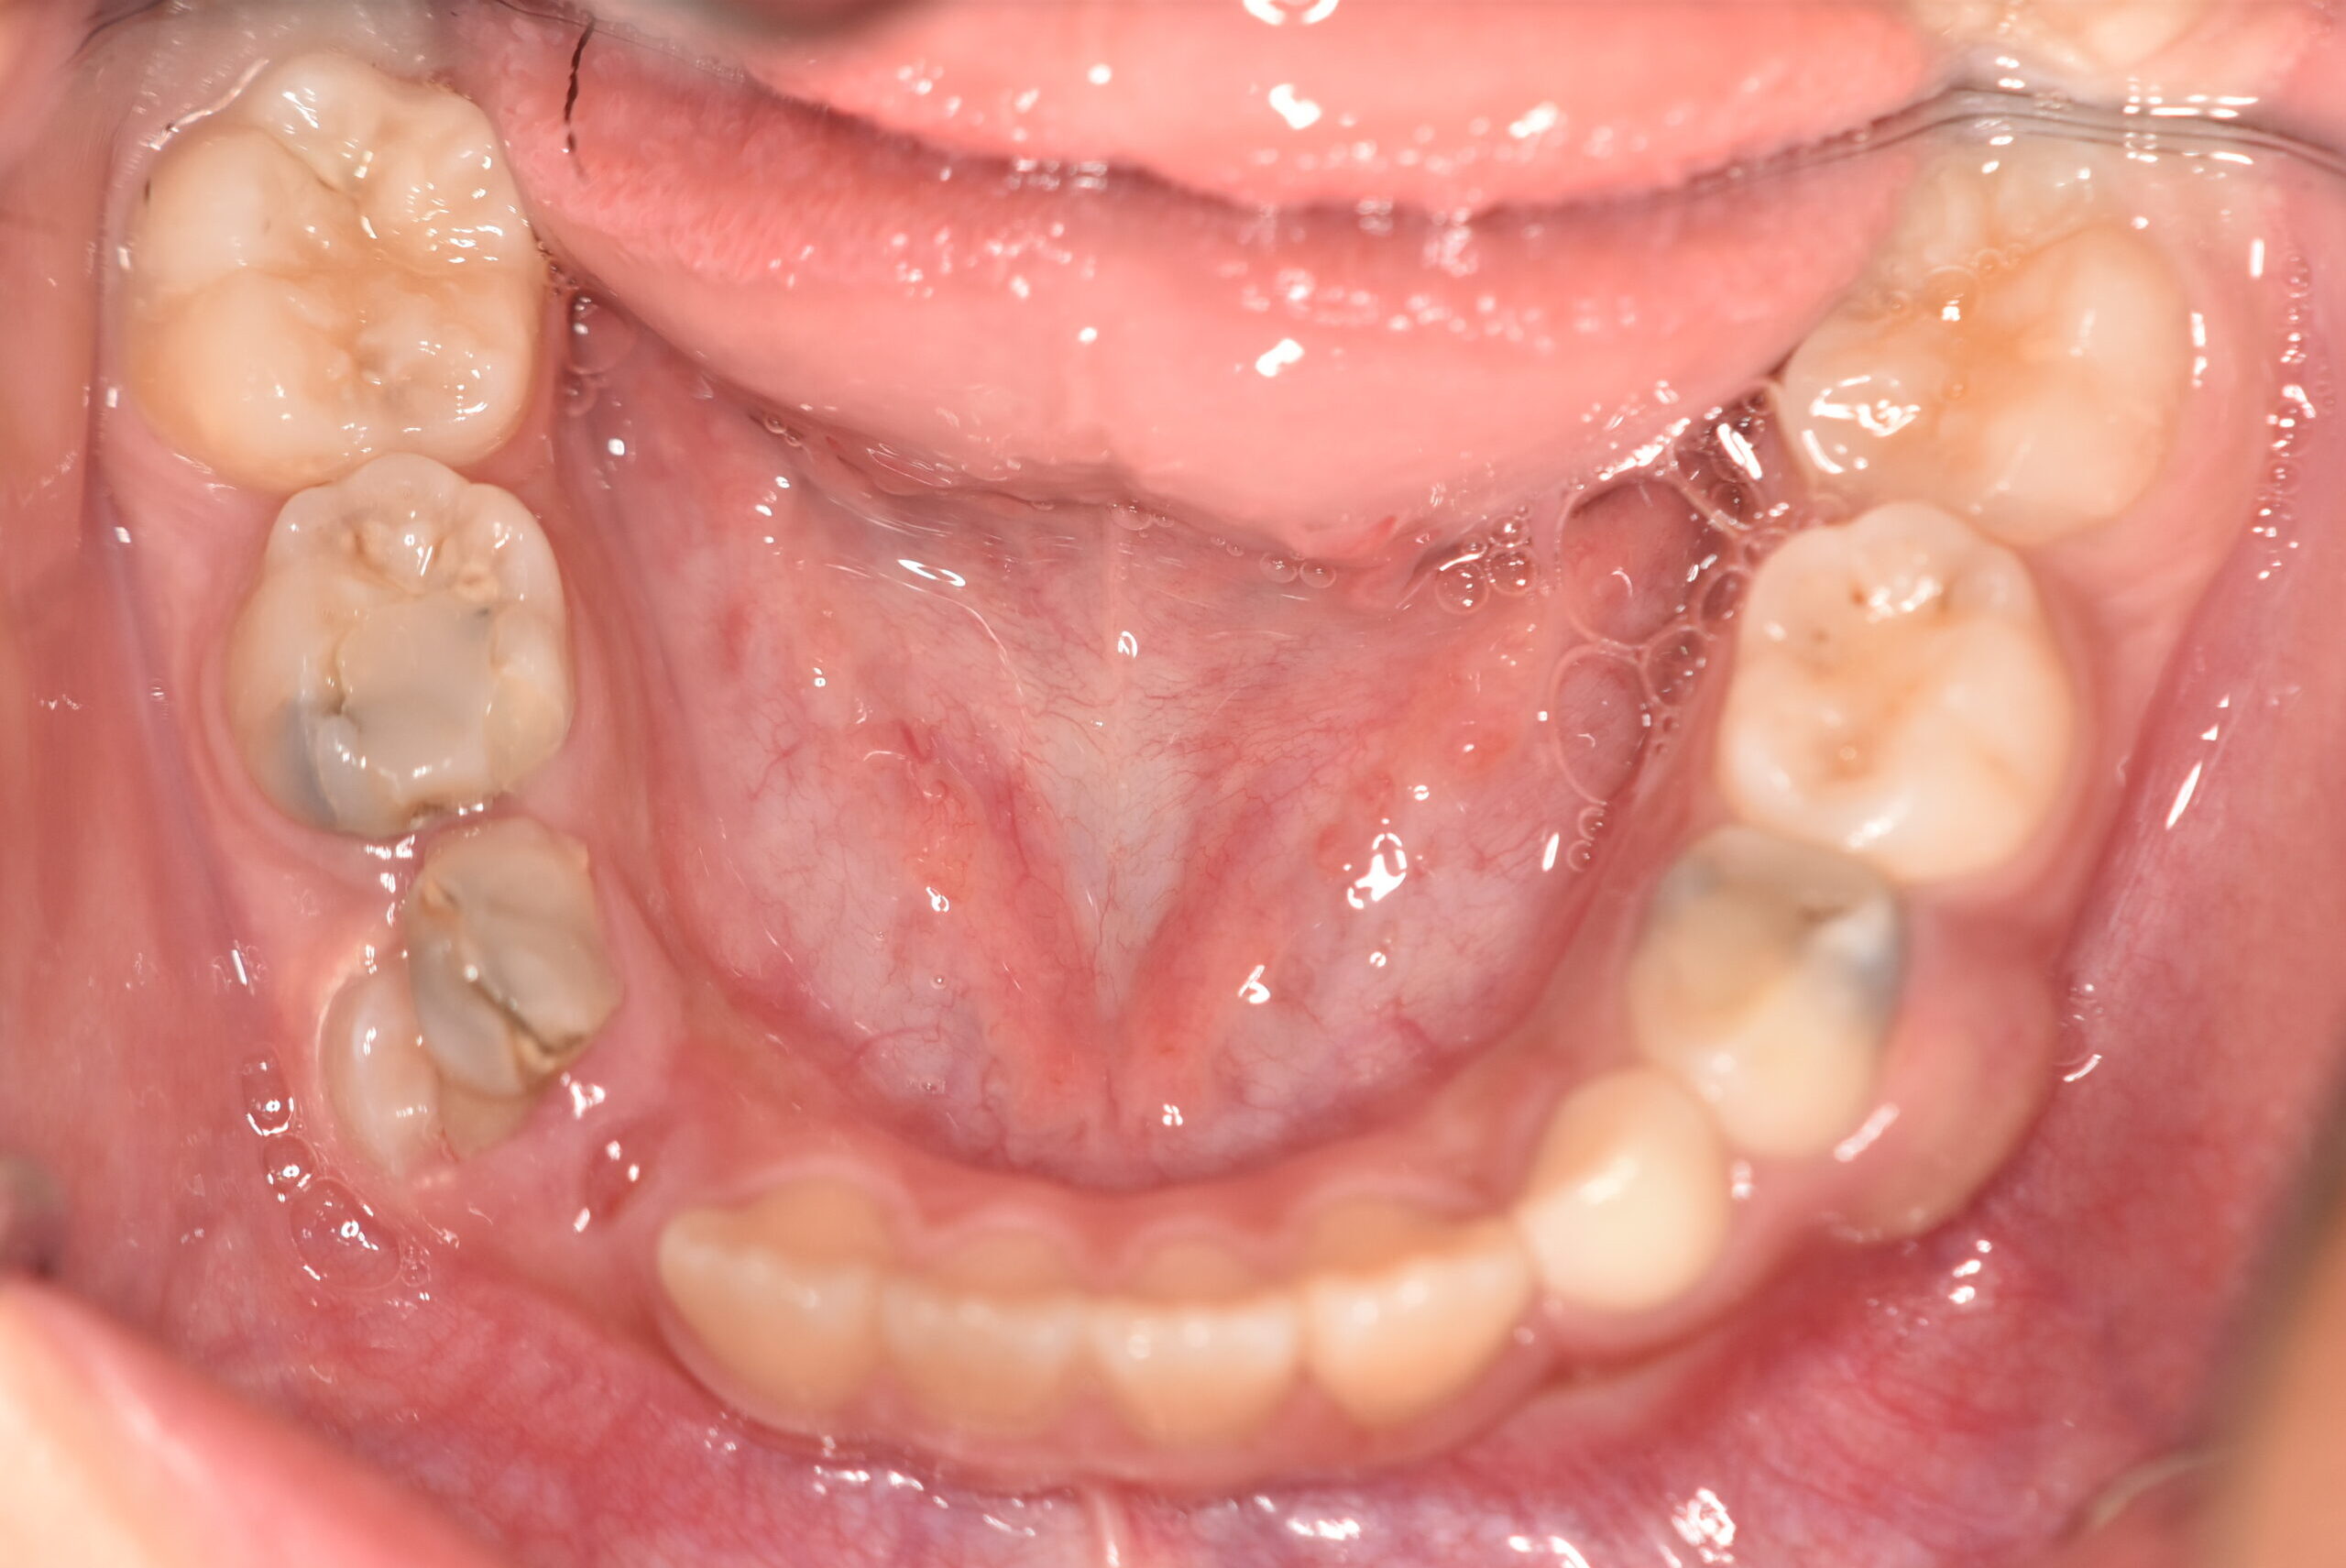

動的治療終了時

症例 症例 症例 症例

治療としてはマウスピース矯正(インビザラインファースト)で配列を行い、上顎の側方拡大と萌出スペースを確保しました。

治療期間は、6ヶ月でした。

今後、側方歯生え変わりまで経過観察を行います。